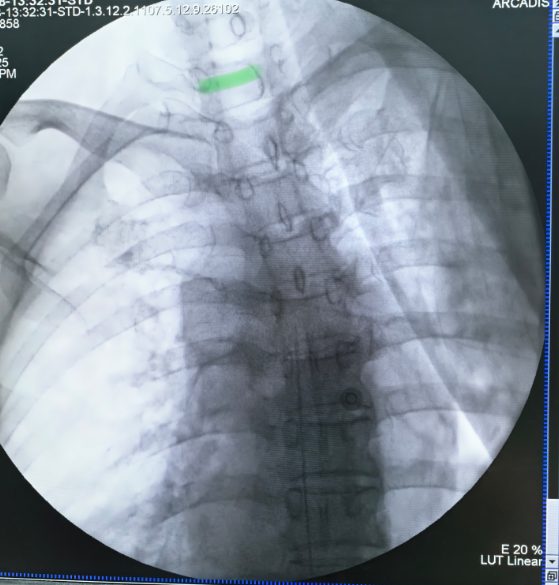

治疗:于2025年7月28日行IDDS手术,将导管头端置于T5水平,术后给予鞘内镇痛(盐酸氢吗啡酮20mg+盐酸罗哌卡因0.2g+生理盐水60ml共100ml,持续量0.1ml/h、追加量0.3ml,间隔15min),截止到术后第一天查房,疼痛控制稳定,停用芬太尼透皮贴。术后第二天查房,原疼痛部位基本无痛,停用静脉PCA泵,每日鞘内镇痛用量仅为4ml。继续观察两天,患者疼痛症状以及不良反应基本缓解,于2025年8月1日办理出院。

图2 术中C臂辅助导管定位,导管位于T5水平